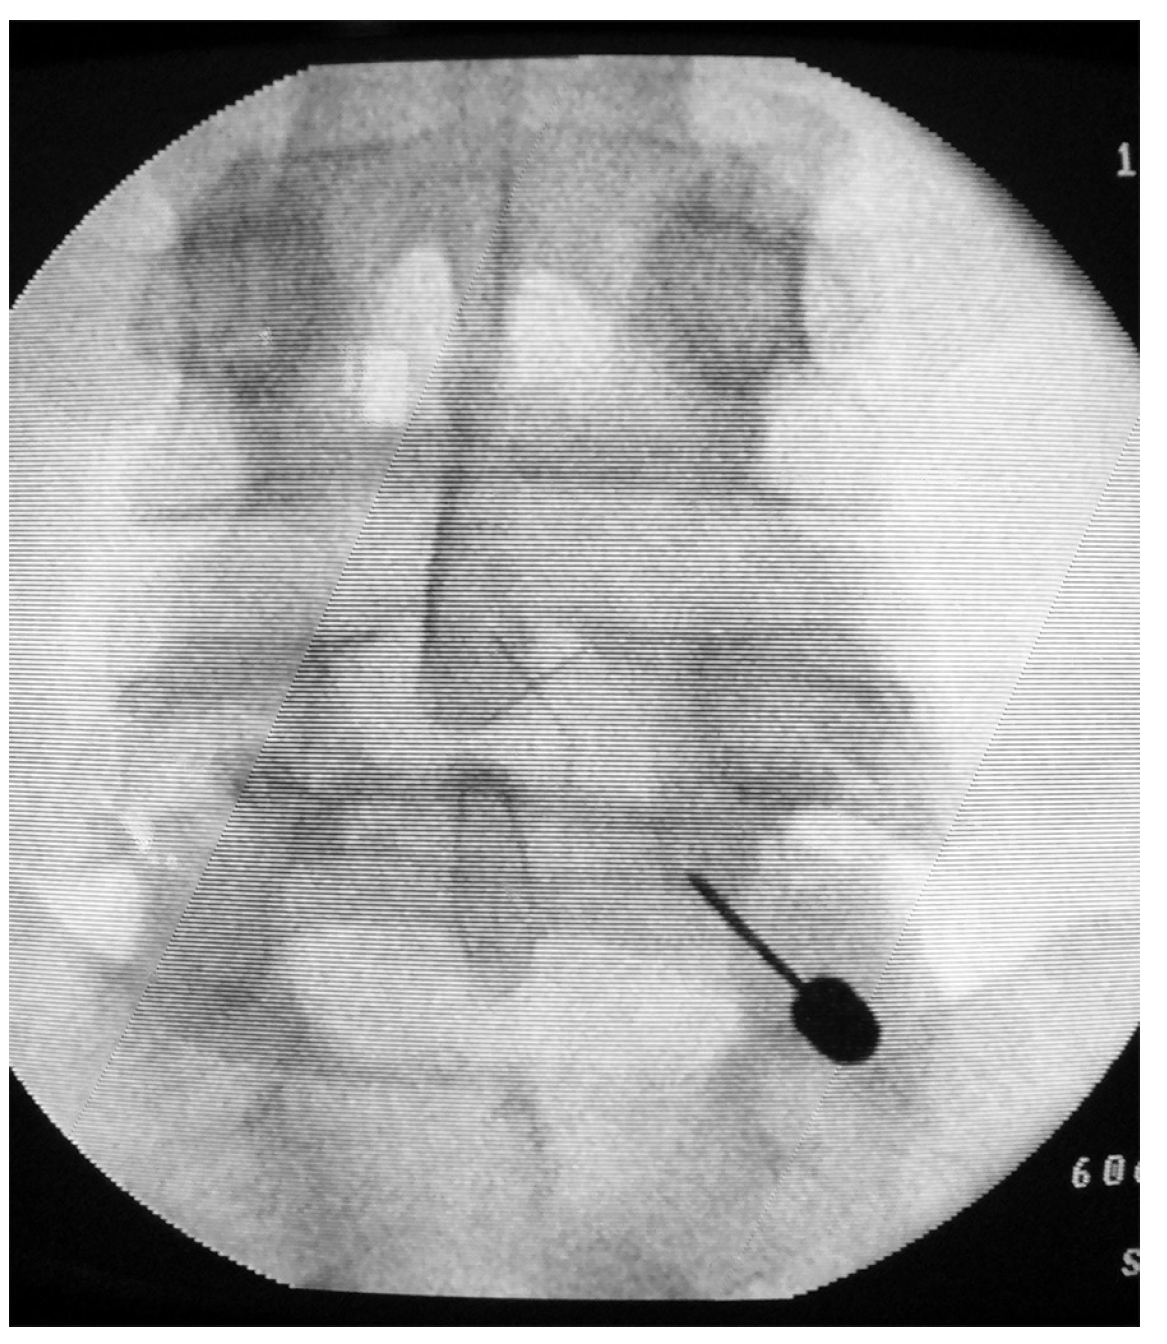

F. Debusscher и S. Troussel [7] считают, что с целью дифференциации болевого синдрома и прогнозирования эффекта хирургического лечения пациентам следует выполнять двухстороннюю тест-блокаду зоны спондилолизных дефектов местным анестетиком длительного действия (0,5% раствором левобупивакаина). Для ее выполнения с целью контроля положения иглы необходимо использовать электронно-оптический преобразователь (ЭОП) или рентген-контроль (рис. 1). При отчетливом положительном эффекте на местную анестезию даже в виде кратковременного купирования болевого синдрома следует рассчитывать на благоприятный результат оперативного лечения. При этом блокада действенна только при отсутствии нестабильности пораженного ПДС, так как болевой синдром после анестезии зоны спондилолиза может сохраниться за счет патологической подвижности позвонка.

Рис. 1. Блокада области правого спондилолизного дефекта L5 позвонка

Если боль после выполнения блокады существенно не уменьшается, хирургическое лечение по предлагаемой методике не проводится.